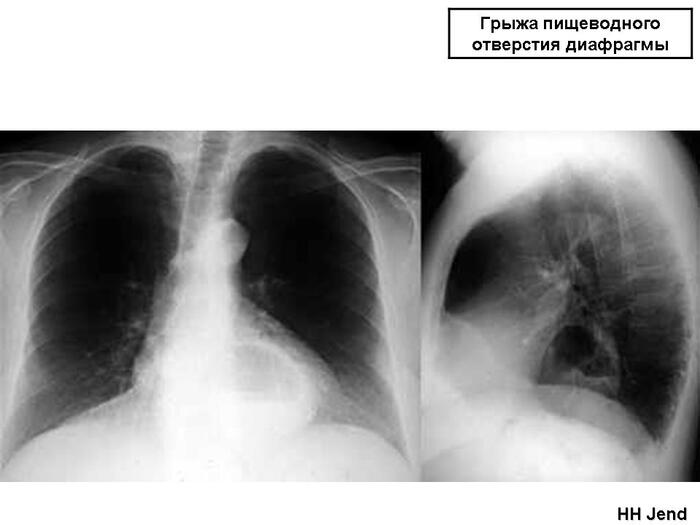

19 - Изменения диафрагмы, не связанные с плевральной патологией (диафрагмальная грыжа, высокое стояние диафрагмы и т. д.).